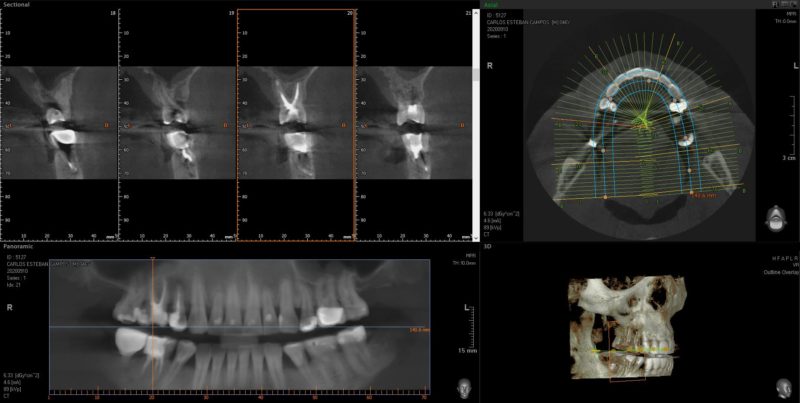

El primer paso y más importante es elaborar un buen diagnóstico: te haremos exploración, pruebas de vitalidad pulpar en clínica y utilizaremos las últimas herramientas digitales, como el escáner 3D y radiología digital, que nos dará la máxima información con la mínima radiación.